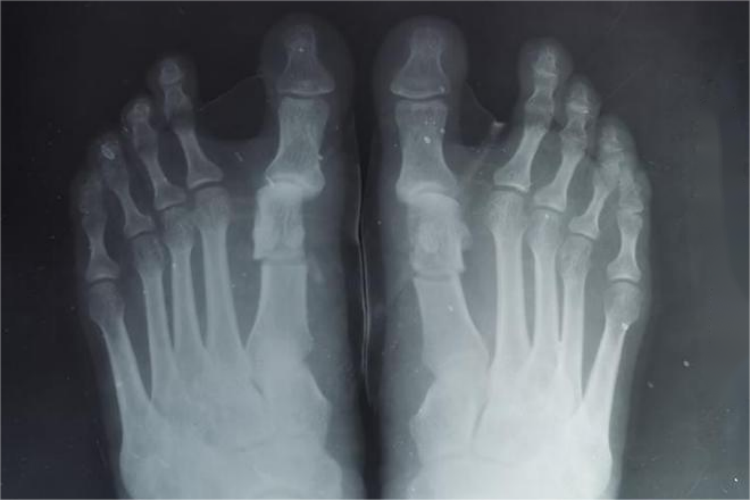

脚掌CT可清楚观察到脚部结构,包括7块跗骨、5块跖骨和14块趾骨。骨皮质呈致密的线状、带状影,骨小梁表现为细密的网状影,骨髓腔呈低密度;还可显示关节骨端和骨性关节面,呈线状高密度影;影像中观察软组织结构,能区分肌肉、脂肪、血管等。